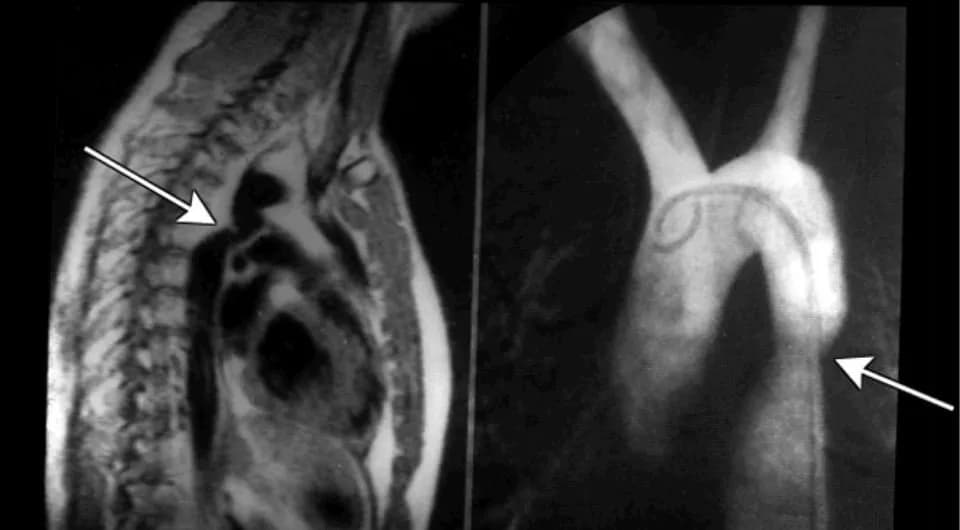

• Siêu âm Doppler tim: Thường hữu ích ở trẻ nhỏ, ở người lớn thì khó đánh giá hơn. Trên siêu âm có thể xác định vị trí của chỗ hẹp, đo được chênh áp qua eo động mạch chủ, phát hiện các bất thường bẩm sinh phối hợp như van động mạch chủ hai lá van, tắc nghẽn đường ra thất trái, hẹp van hai lá…

• Chụp cắt lớp vi tính động mạch chủ: Là phương tiện quyết định chẩn đoán hẹp eo động mạch chủ ở người lớn. Trên phim chụp xác định được vị trí, hình thái chỗ hẹp, các tuần hoàn bàng hệ và các tổn thương phối hợp.

• Thông tim chẩn đoán: Đưa các dụng cụ qua đường mạch máu ngoại biên (động mạch đùi hoặc động mạch quay) để chụp chỗ hẹp và tuần hoàn bàng hệ. Hẹp eo động mạch chủ được chẩn đoán khi chênh áp trên 10mmHg giữa động mạch chủ lên và động mạch chủ xuống. Tuy nhiên chênh áp không phản ánh mức độ hẹp vì có thể ảnh hưởng bởi các tuần hoàn bàng hệ.

Chẩn đoán hẹp eo động mạch chủ dựa trên X-quang.